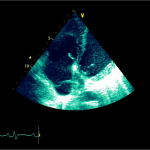

Ecocardiografia transtoracică

- Formaţiune hiperecogenă cu suprafaţa neregulată, care tapetează peretele liber al VD, grosime de 12 mm

- Dispusă de sub planul valvei tricuspide până in apropierea conului de ejecţie al valvei pulmonare

- SIV aplatizat

Ecografia transesofagiană:

Confirmă datele de la ecografia transtoracică